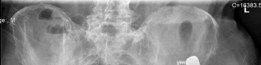

For anyone wondering about Acetabular Revision: Solving Challenges Post Two-Stage Arthroplasty, A **title acetabular revision** is a complex procedure addressing issues like septic loosening, dislocation, and significant osteolysis in total hip arthroplasty. For a 71-year-old male with a dislocated left THA due to infection and periacetabular bone loss, treatment involved a two-stage exchange followed by revision with a press-fit hemispherical cup and screw fixation.

Standard anteroposterior pelvis and cross-table lateral radiographs are mandatory. Judet views (iliac and obturator obliques) are critical for assessing the integrity of the anterior and posterior columns. However, plain radiography often underestimates the extent of osteolysis and bone loss.

High-resolution Computed Tomography with Metal Artifact Reduction Sequence is essential for three-dimensional evaluation of the remaining bone stock. Computed Tomography allows for the definitive diagnosis of pelvic discontinuity, the assessment of the medial wall, and the quantification of ischial and iliac bone available for fixation.